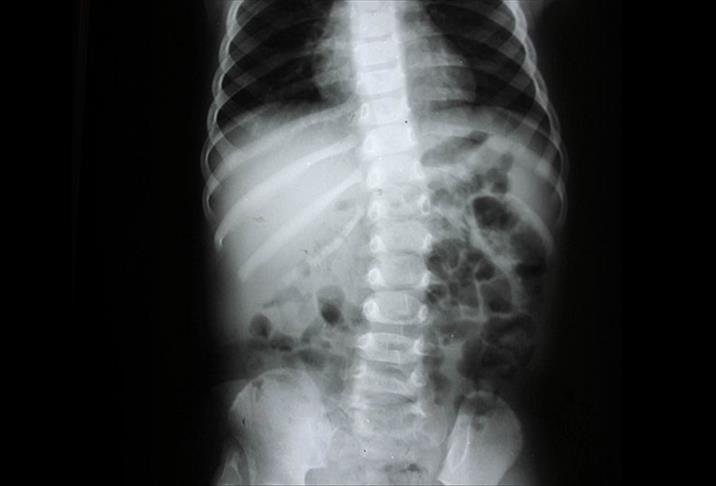

Fark edilmeyen, ihmal edilen çok hasta olduğunu dile getiren Prof. Dr. Yücesoy, gerekli önlem alınmadığı takdirde hastanın ilerleyen yaşlarda bel ağrısı veya fıtık şikayetiyle doktora başvurduğunu, bir röntgen filmiyle de altta yatan nedenin "skolyoz" olarak belirlendiğini bildirdi.

Skolyozun toplumda rastlanma sıklığının yüzde 1-2 arasında değiştiğine işaret eden Kemal Yücesoy, "Skolyozda sadece o kemiğin çıkarılması ve altının ve üstünün birbirine bağlanması sonra meydana gelebilecek daha büyük rahatsızlıkları önlüyor.40-45 derece gibi ileri boyutta eğrilik olduğunda ise bunu rijit sistemlerle, vidalarla ve ona bağlı çubuklarla düzeltiyoruz" diye konuştu.

Eğriliğin erken dönemde fark edilmesi durumunda fizik tedavi, korse gibi yöntemlerle düzeltilebileceğini anlatan Yücesoy, yüzde 20 eğrilik döneminde bükülmeyi izlediklerini, yüzde 20 ve 45 eğrilik düzeyinde fizik tedavi, egzersiz ve korse uygulamaları önerdiklerini, eğim arttıkça ameliyatı tercih ettiklerini ifade etti.